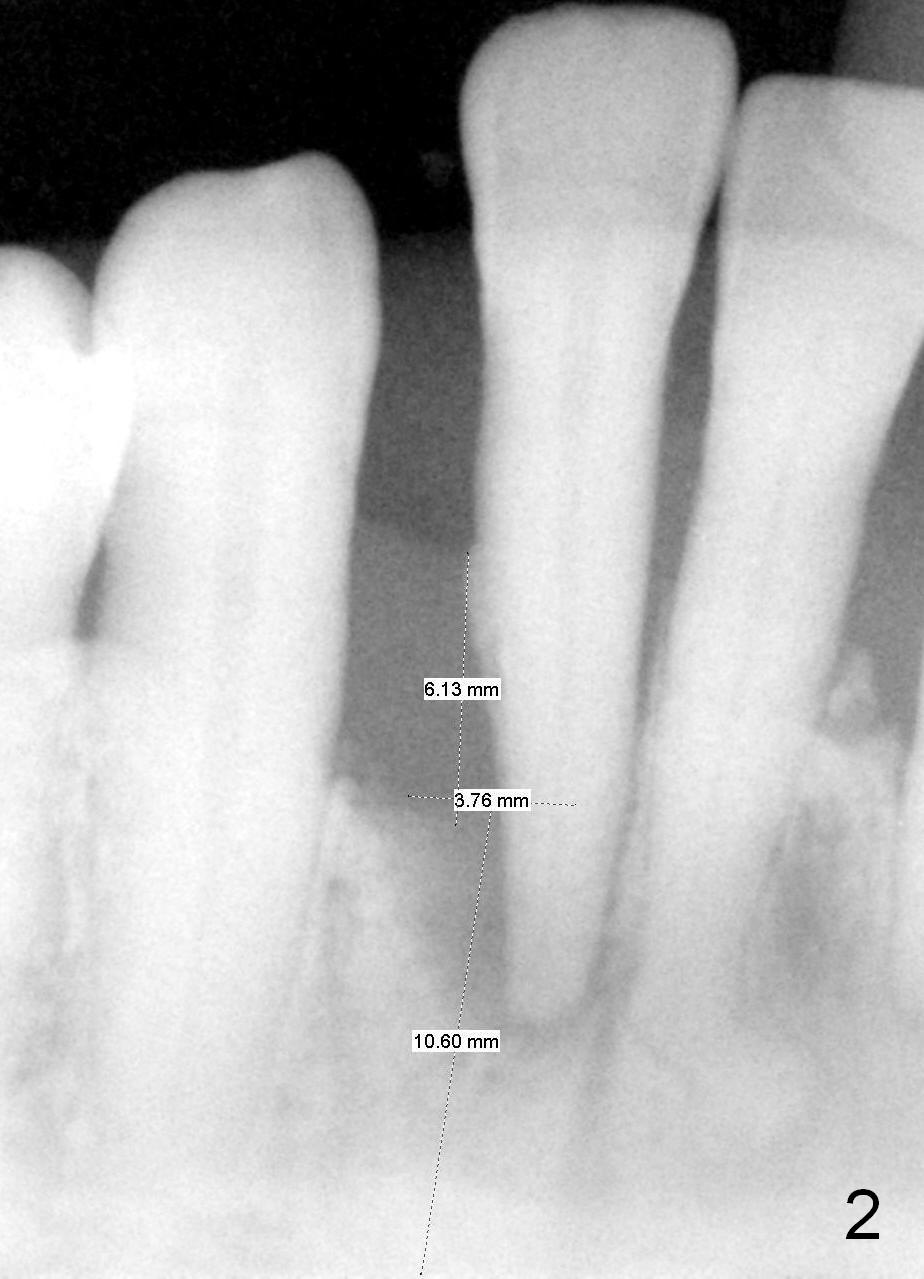

A 65-year-old lady has history of poliomyelitis and use of injection osteoporosis medicine. The tooth #26 is periodontally affected (Fig.1). Since the sensor is not placed deep enough (or there is plenty space above (Fig.1 arrow)), it is difficult to design implant treatment plan (Fig.2). PA has to be taken immediately pre-operatively for precise design.

A tentative design is as follows: a bone-level implant is placed 4 mm subgingival (Fig.3, total gingival height 6 mm (Fig.2)). The cuff will be 4 mm. The most coronal threads are covered by bone graft (red circles).